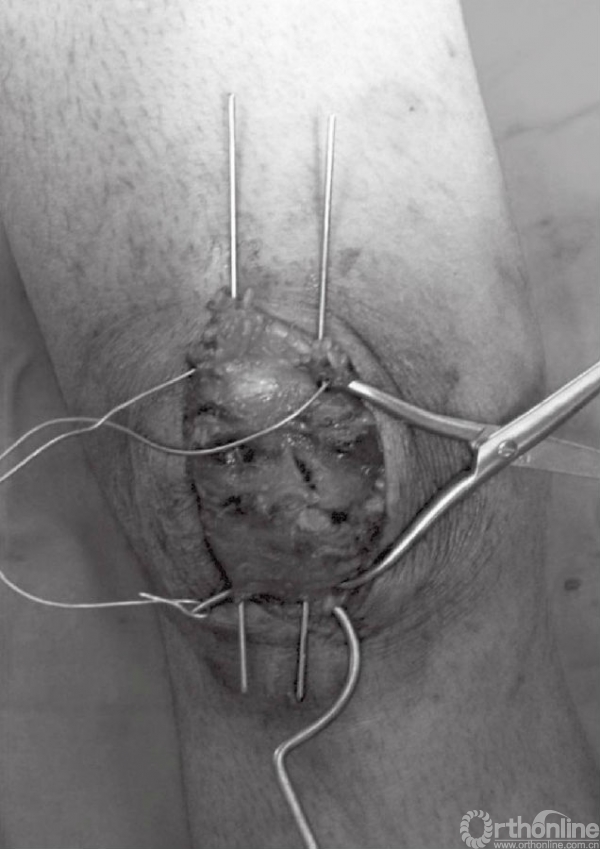

在张力带旋紧固定后,用钢丝剪剪除多余钢丝。突出的部分折弯后贴近髌骨上极放置(图15)。克氏针末端用折弯器折弯后尽量贴近髌骨表面。钢丝末端旋转后经股肌间隙埋入股四头肌腱(图16)。后期缝合肌间隙,可防止克氏针退出。克氏针远端在近髌骨处切断(图17)。用不可吸收线缝合撕裂的支持带(图18)。屈膝90°,以评估内固定的稳定性(图19)。

图18 在髌骨两侧用不可吸收缝线缝合撕裂的支持带